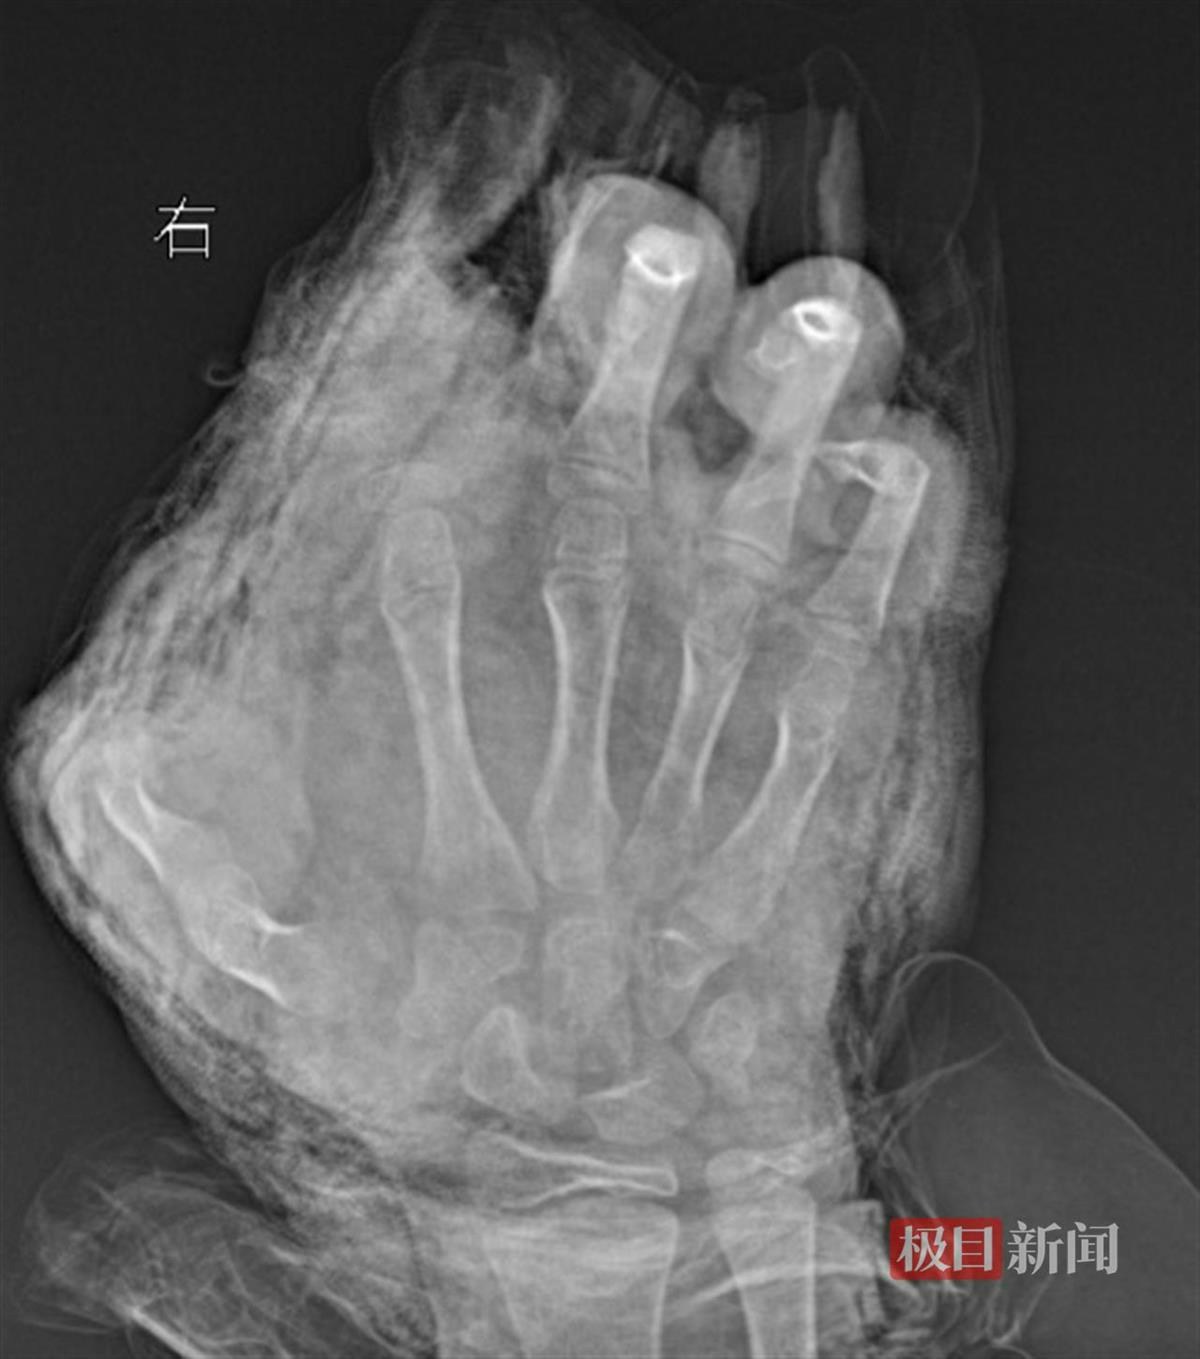

+ P) B4 G) p- v+ f/ r1 a公仔箱論壇男童被炸斷3根手指。(極目新聞)

2 `$ D' b3 a( m7 E$ B5.39.217.76「孩子來院時,傷得觸目驚心。」武漢市第四醫院小兒創傷及矯形中心副主任醫師徐劍表示,明明雙手血肉模糊,臉部及胸前亦有炸裂傷,其中右手虎口嚴重撕裂,傷口內嵌入小石子。經進一步檢查發現,他的右手食指完全離斷,拇指前段二分之一處被炸斷,中指遠節軟組織缺損,環指及小指指腹亦嚴重炸傷。( m# h# I8 `+ O3 ~ I

為防止傷口感染及二次壞死,醫療團隊於5日晚間11時進行緊急清創手術。徐劍醫生透露,手術中,團隊剝離拇指壞死組織的同時,細心保護尚存的細小血管,以最大程度挽救其右手拇指的功能。手術持續至6日凌晨3時結束,但由於傷勢嚴重,離斷的食指因血管及肌腱撕裂過於嚴重,無法再植,後續仍需進行二次清創及修復手術。